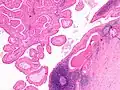

The appearance of this tumor under the microscope is unique. There are cystic spaces surrounded by two uniform rows of oncocytes, which are epithelial cells with abundant, granular, eosinophilic cytoplasm.[6] The cystic spaces have epithelium referred to as papillary infoldings that protrude into them. Additionally, the epithelium has lymphoid stroma with germinal center formation.

This Warthin's tumor presented as a parotid mass in a middle-aged male, who underwent superficial parotidectomy. The tumor, at the right of the image, is well-demarcated from the adjacent parotid tissue and tends to shell out from it.

Histopathology of Warthin tumor in the parotid gland. Another view of a file "Warthin tumor (1).jpg". H&E stain.

Intermediate magnification micrograph of a Warthin tumor.